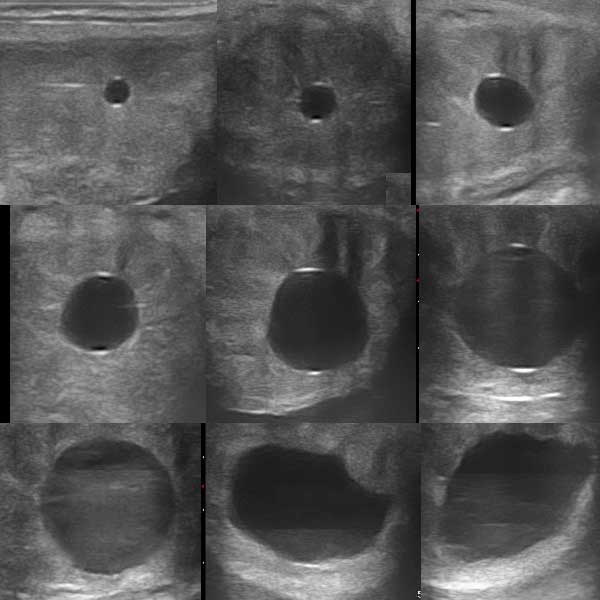

Szaporodásbiológia

- Ciklusdiagnosztika

- Embrionális fejlődés követése

- “Babamozi”

- Ovum Pickup ( OPU, petesejt leszívás)